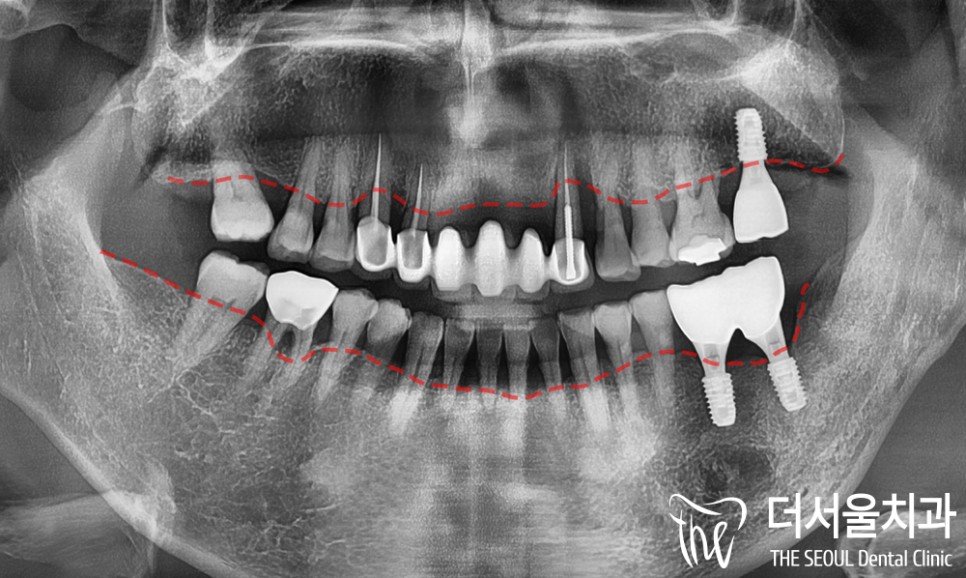

어라? 문제는 여기서 끝이 아니였는데요.

위쪽과 더불어 아래쪽에도 문제가 있었습니다.

치경부 마모는 물론이며

잇몸이 내려앉아 있었는데요.

파노라마로 살펴보니

이곳에서도 심한 염증이 관찰되었습니다.

최종적으로

上 – 앞니임플란트

下 – 브릿지 수복

이렇게 치료를 돕기로 했습니다.